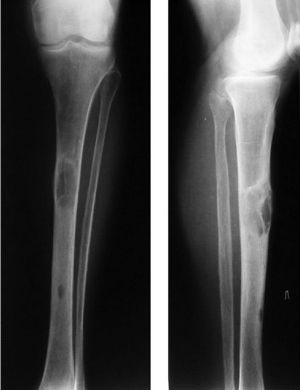

Самой распространенной и необъяснимой формой выступает фиброзная остеодистрофия. Ей свойственно очаговое рассасывание костной ткани с дальнейшим трансформированием в соединительнотканную структуру. Эта форма до конца не изучена, лишь имеется описание клинического проявления. Оно характеризуется своеобразным утолщением кости в определенных местах. На начальных этапах поврежденная зона ничем не отличается, однако спустя определенный промежуток времени пациент ощущает боли. Костная ткань деструктируется, а в местах повреждения отмечается припухлость плотной и эластичной консистенции, обнаруживаемая во время пальпирования.

К симптоматической картине относится деформация костей и наличие патологических переломов рук и ног. В дополнение к этому добавляется болезненность в костях при физнагрузке, даже при незначительной (подъем кружки с чаем).